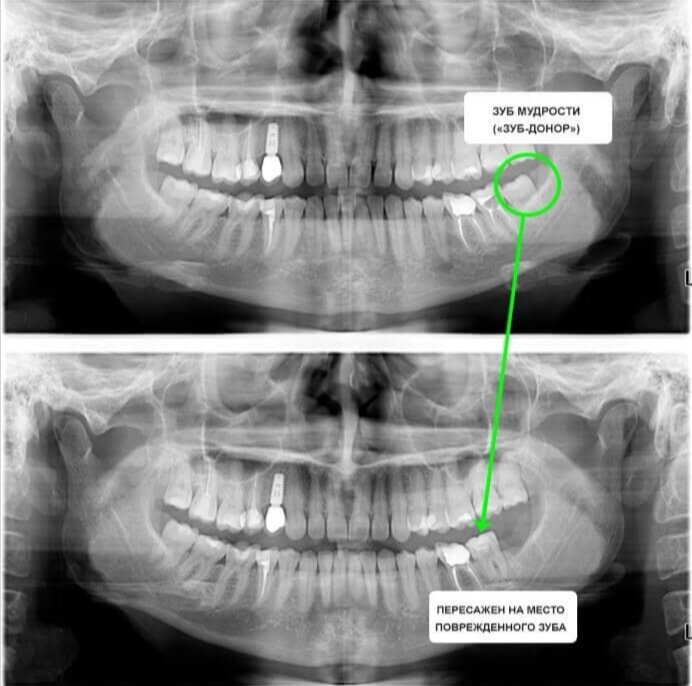

Трансплантация зубов - какой зуб удается имплантировать

Как правило, лучше всего имплантировать зуб, который находится в зоне видимости, например, передние резцы или клыки, так как их потеря может существенно повлиять на эстетический вид и уверенность в себе. Кроме того, эти зубы играют важную роль в процессе пережёвывания пищи и в произношении ряда звуков. Однако современные технологии позволяют успешно восстанавливать и боковые зубы, что открывает возможность для полноценного жевания и распределения нагрузки на челюсть, предотвращая её деформацию.